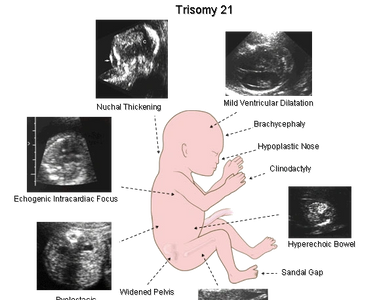

There are a number of potential nonstructural or minor markers which may be seen at the time of the fetal anatomic scan around 20 weeks. These findings may sometimes indicate an underlying chromosome abnormality, like Down syndrome or other fetal abnormality, but are most often seen as a normal variant. As an isolated finding, these findings usually do not significantly change the risk. They are simply a reminder to take a good look at the baby. Also correlate with your first trimester screen or any other screening you might have had. For extra additional reassurance, you might choose an NIPT test to confirm the chromosomes are normal.

The most common markers include: